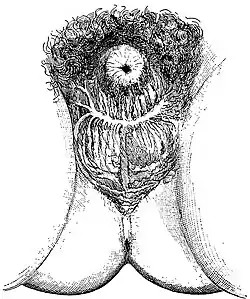

There were two kinds of castration: the "lesser seal" and the "greater seal". For men, the "lesser seal" meant the removal of the testicles only, while the "greater seal" involved either removal of the penis or emasculation (removal of both penis and testicles). Men who underwent the "greater seal" used a cow-horn when urinating. The castrations and emasculations were originally performed with a red-hot iron, called the 'fiery baptism'. However, the skoptsy later transitioned to using knives or razors, with the iron serving only to stop the bloodflow. They also twisted the scrotum, destroying the seminal vesicles and stopping the flow of semen.

In women, the Skoptsy removed the nipples or the whole breasts. Occasionally, they simply scarred the breasts. They also often removed the labia minora and clitoris. They did not use anesthetics.[3]